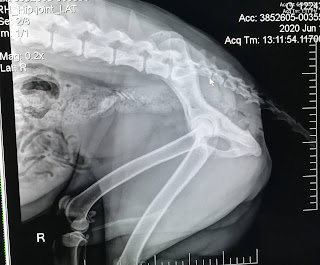

Last night he was acting kinda weird but I thought maybe it was because he was too hot (we don't have air conditioning). This morning he refused to stand on his right leg and he yelped when we lifted him by his middle section ☹️ we took him to an emergency clinic and they did tons of x-rays. I guess he pinched/twisted a nerve in his spine and he needs 2 weeks rest. Hopefully he'll be ok. I was worried it was hip dysplasia or something worse.

Official diagnosis: pinched nerve in Rottsky's back